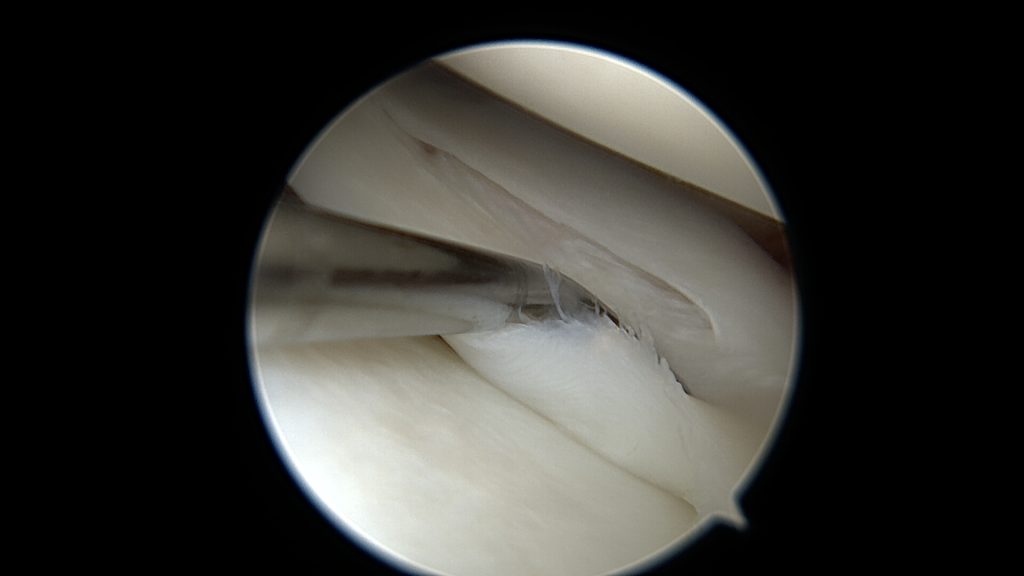

W tym przypadku jej proste przyszycie nie będzie możliwe, nie będzie po prostu stabilnych fragmentów łąkotki które można złapać szwem. Konieczne jest zastosowanie techniki „biokanapki”. Zabieg polega na owinięciu błoną kolagenową uszkodzonego fragmentu łąkotki, błona pełni tu rolę worka trzymającego włókna łąkotki razem. Szwy zakłada się poprzez błonę kolagenową stabilizując tym samym luźne uszkodzone fragmenty łąkotki. Na koniec zabiegu podaje się komórki macierzyste do środka stworzonej w ten sposób przestrzeni. Postępowanie pozabiegowe jest w tym przypadku określone odpowiednim protokołem rehabilitacyjnym.